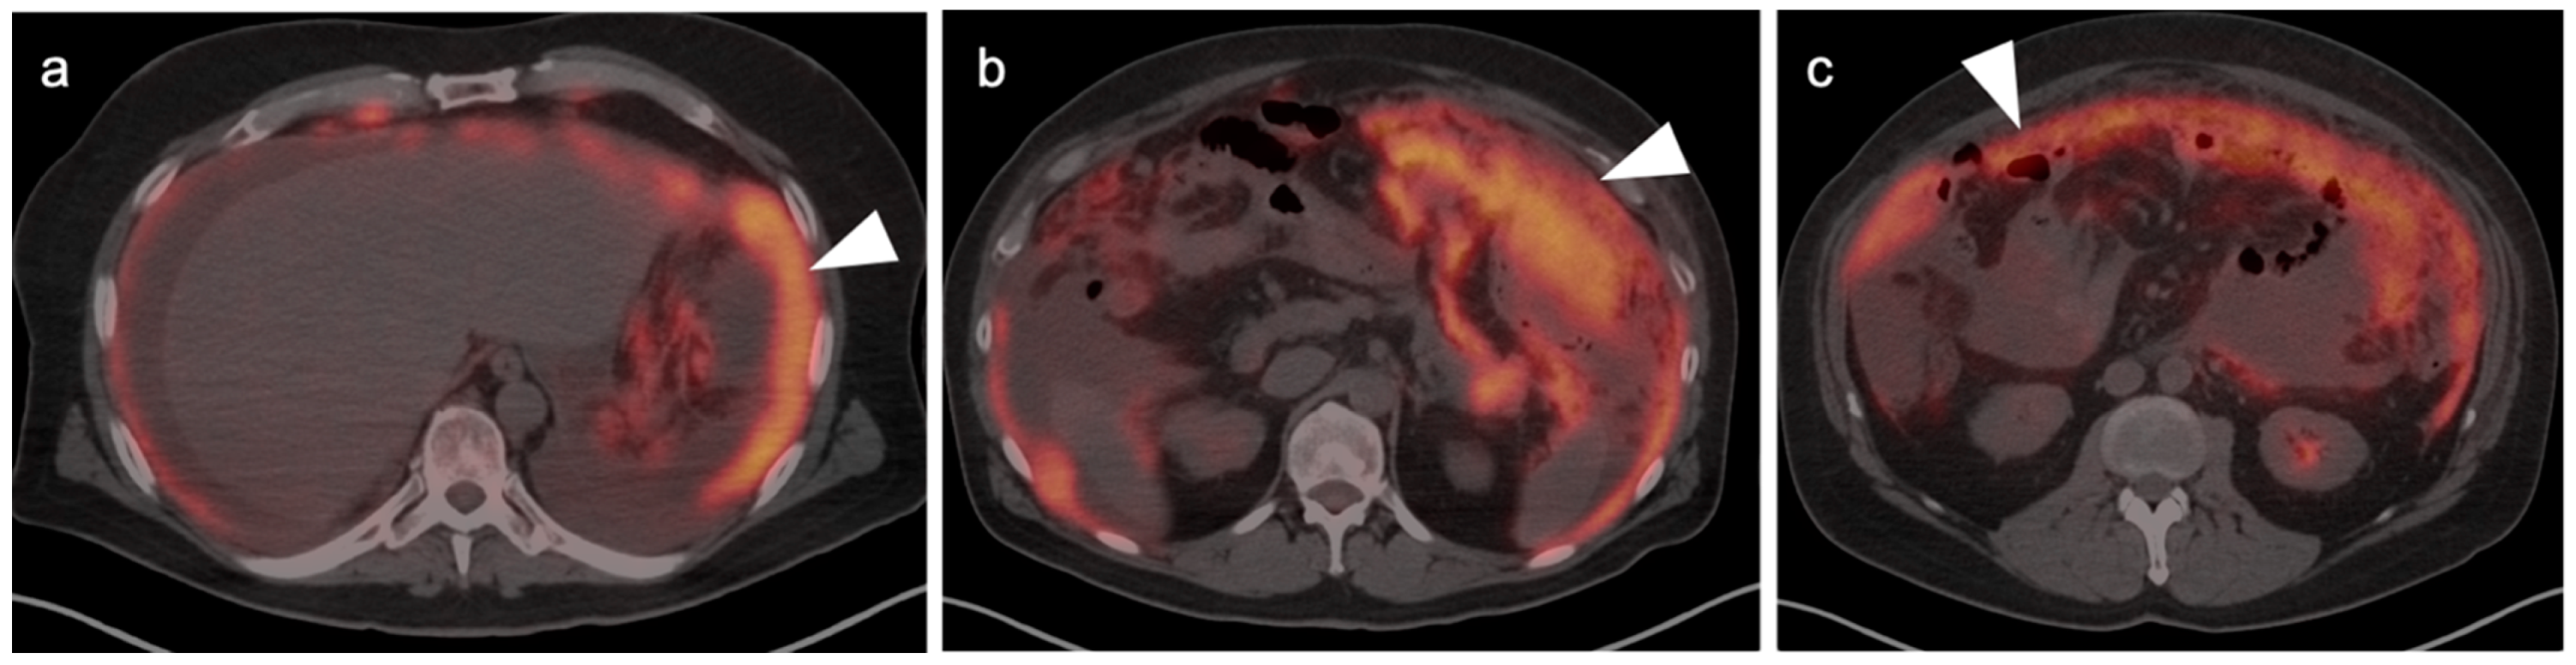

5. Cholangiocarcinoma